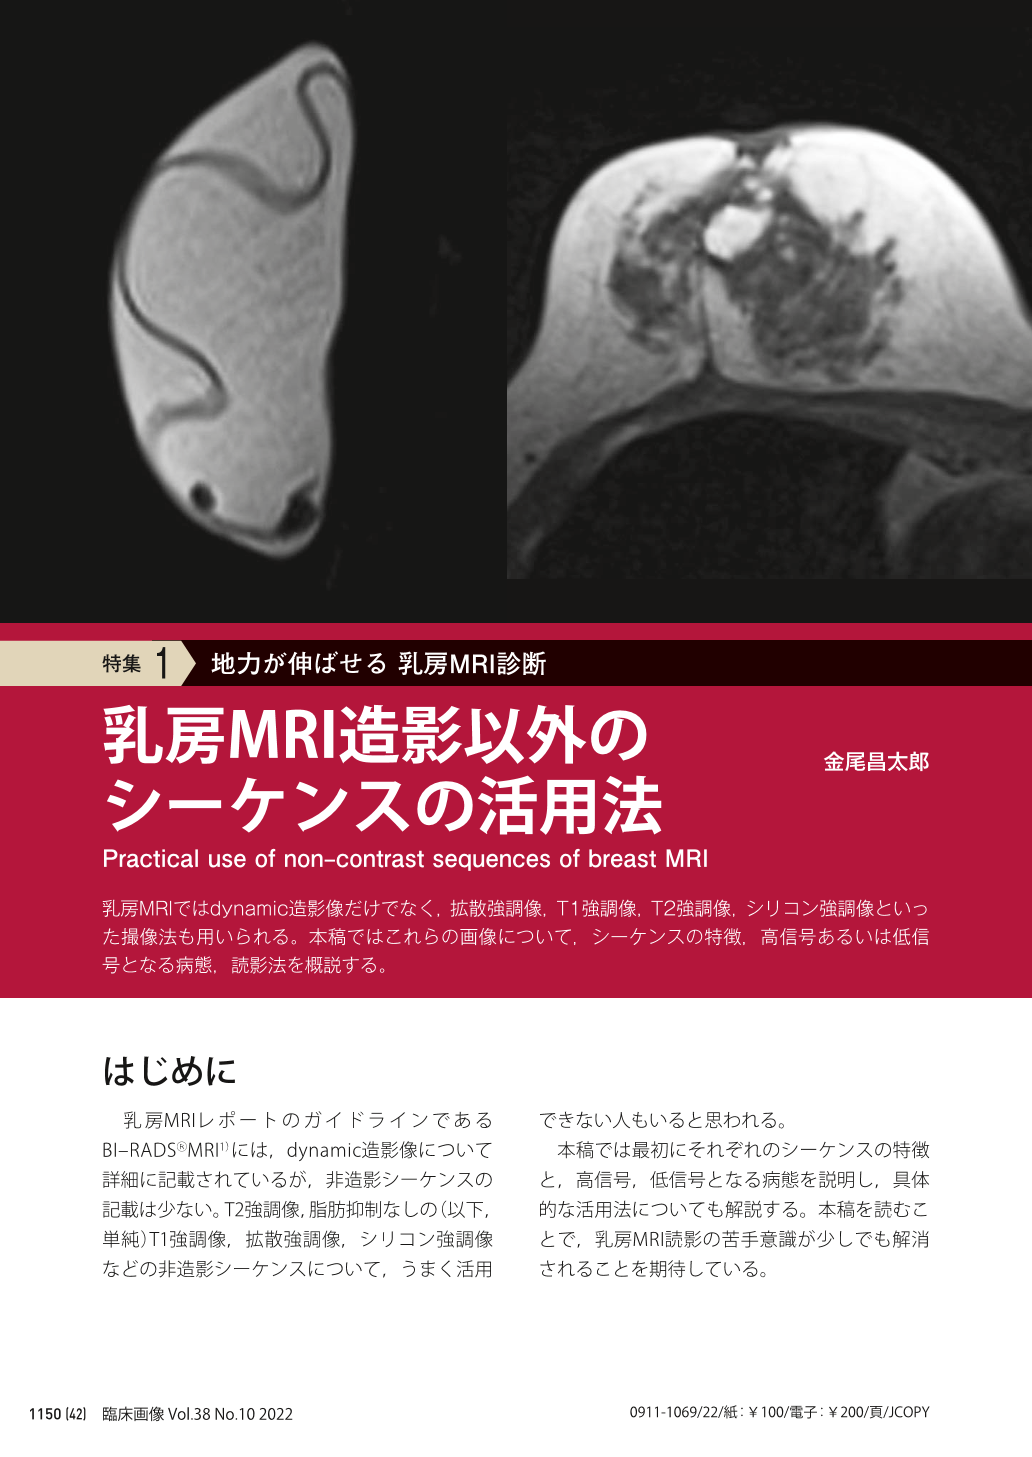

乳房MRIアトラス | 五味 直哉, 菊池 真理, 五味 直哉, 菊池 真理。乳房MRIアトラス 裁断済 書き込みなし 乳腺MRI。乳房MRIアトラス 裁断済 書き込みなし 乳腺MRI 本。人気アルファ米5種セット 25袋。婦人科MRIアトラス 改訂第2版 (画像診断 別冊KEYBOOKシリーズ。乳房MRI撮影・読影の基礎とコツ (臨床画像 38巻10号) | 医書.jp。乳房MRI | 那珂川市の病院ならCT・MRI検査が可能な吉田。ご覧いただきありがとうございます!専用の機械で裁断してありますが、素人裁断のものです。1ページずつバラバラになってます。裁断済みである事がご理解いただける方のみ購入してください。『裁断済み』のため状態を『傷や汚れあり』にしていま「乳房MRIアトラス」五味 直哉 / 菊池 真理 / 菊池 真理定価: ¥ 9200#五味直哉 #五味_直哉 #菊池真理 #菊池_真理 #菊池真理 #菊池_真理 #本 #自然/医療・薬学・健康。MRI-乳腺MRIの質と安全性を向上させるSmartExam Breast-技術。乳房MRI検査 獨協医科大学埼玉医療センター 放射線部。乳房MRI造影以外のシーケンスの活用法 (臨床画像 38巻10号。乳房MRIアトラス | 五味 直哉, 菊池 真理, 五味 直哉, 菊池 真理。BI-RADSを克服する・Mass編【造影乳房MRIを読めるようになる。乳腺MRI検査・検診 – AIC八重洲クリニック 乳腺外科